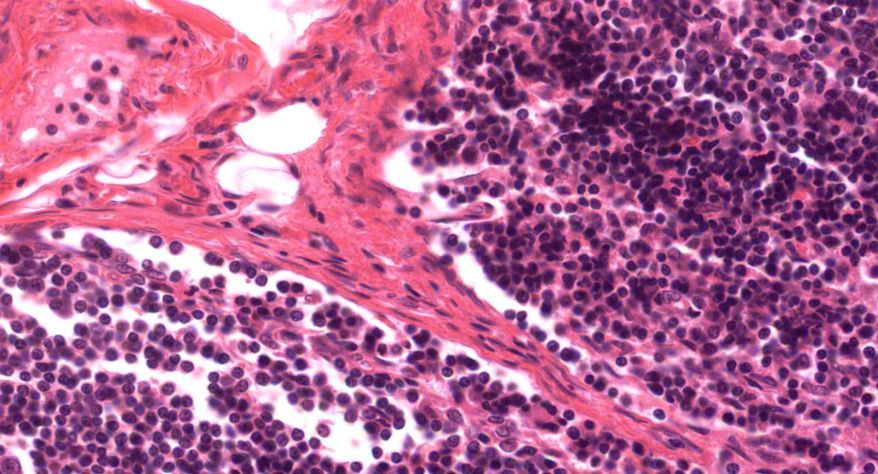

低倍镜:胸腺表面包有薄层结缔组织构成的被膜,结缔组织深入实质,将胸腺分成许多不完整的小叶。每个小叶分为周围的皮质和中央的髓质两部分。皮质中胸腺细胞排列密集,故染色深;髓质中胸腺细胞较少,胸腺上皮细胞多,故染色浅,其中可见染成红色的圆形小体-胸腺小体。高倍镜:胸腺小体大小不等,由几层至十几层扁平的胸腺上皮细胞呈同心圆状排列而成,其外周的细胞较幼稚,细胞核明显;小体中央部分的上皮细胞已退化,细胞核消失,胞质呈均质状,染成红色。

1.成人胸腺全景图

2.被膜

3.皮质

4.髓质

5.胸腺细胞

6.胸腺上皮细胞